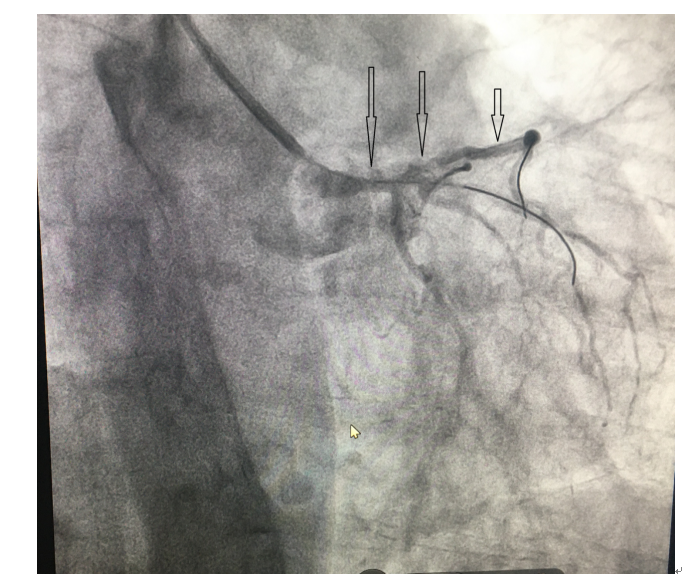

(二)球囊扩张狭窄病变